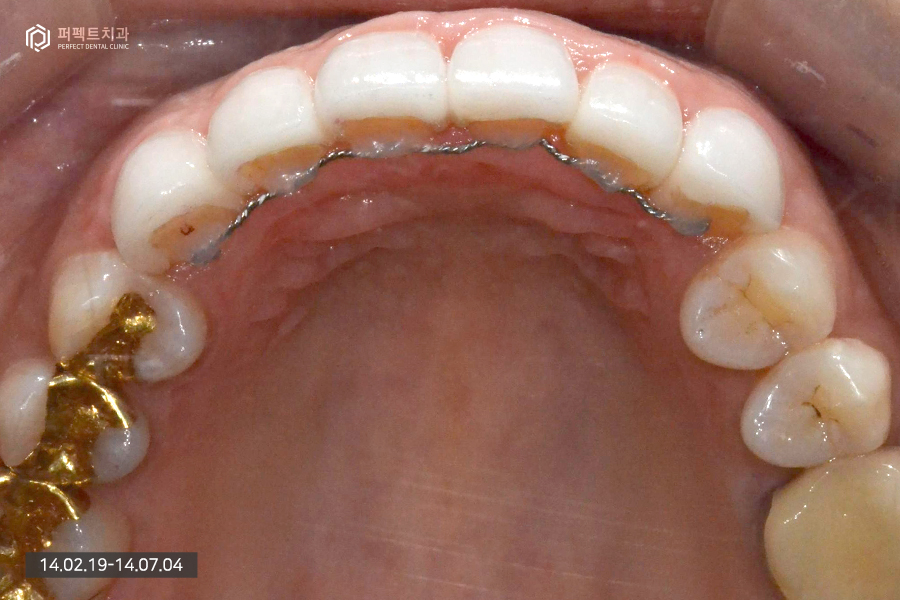

일반적으로 충치의 범위가 큰 경우에는 크라운이라는 치료를 하기도 하는데, 환자분께서는 라미네이트 치료를 원하셨고 부분교정을 같이 진행하신 케이스라 교정 후 치아가 틀어지지 않게 유지장치가 필수로 사용되어야 했습니다.

이 유지장치를 사용할 때 크라운이라는 치료를 하게 되면 크라운에 유지장치를 부착해야 해서 유지장치가 잘 떨어진다는 단점이 있습니다. 하지만 라미네이트 같은 경우 치아의 뒷면은 보철이 아닌 내 치아이기 때문에 유지장치가 잘 유지됩니다.

교정 후에는 이처럼 유지장치가 부착되어 있어야 합니다. 그렇지 않으면 시간이 지나면서 다시 치아가 틀어질 수 있습니다.